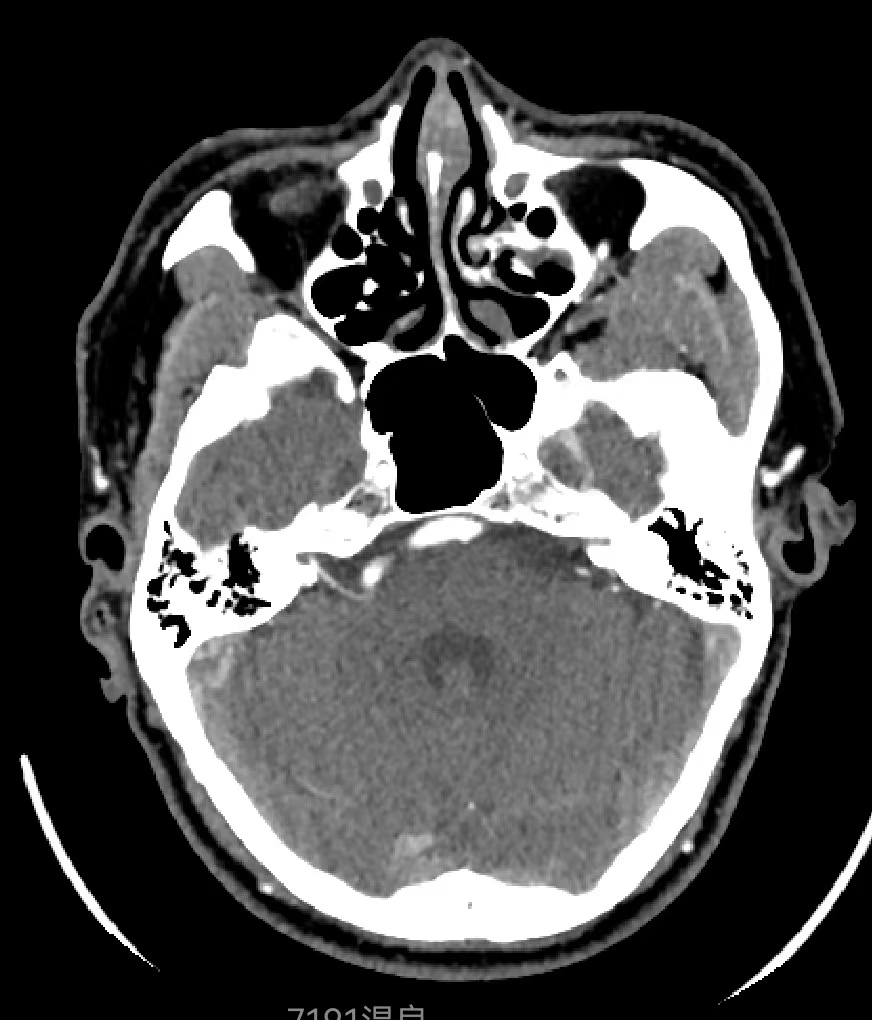

患者,男性,46岁,因“右侧面肌痉挛5年”就诊。查体右侧可见典型的面肌痉挛表现。当地医院MRI可见右侧椎动脉与面神经关系密切,我院行CTA检查可见内听道附近椎动脉扩张、迂曲,与面神经关系密切,与当地医院MRI相符。